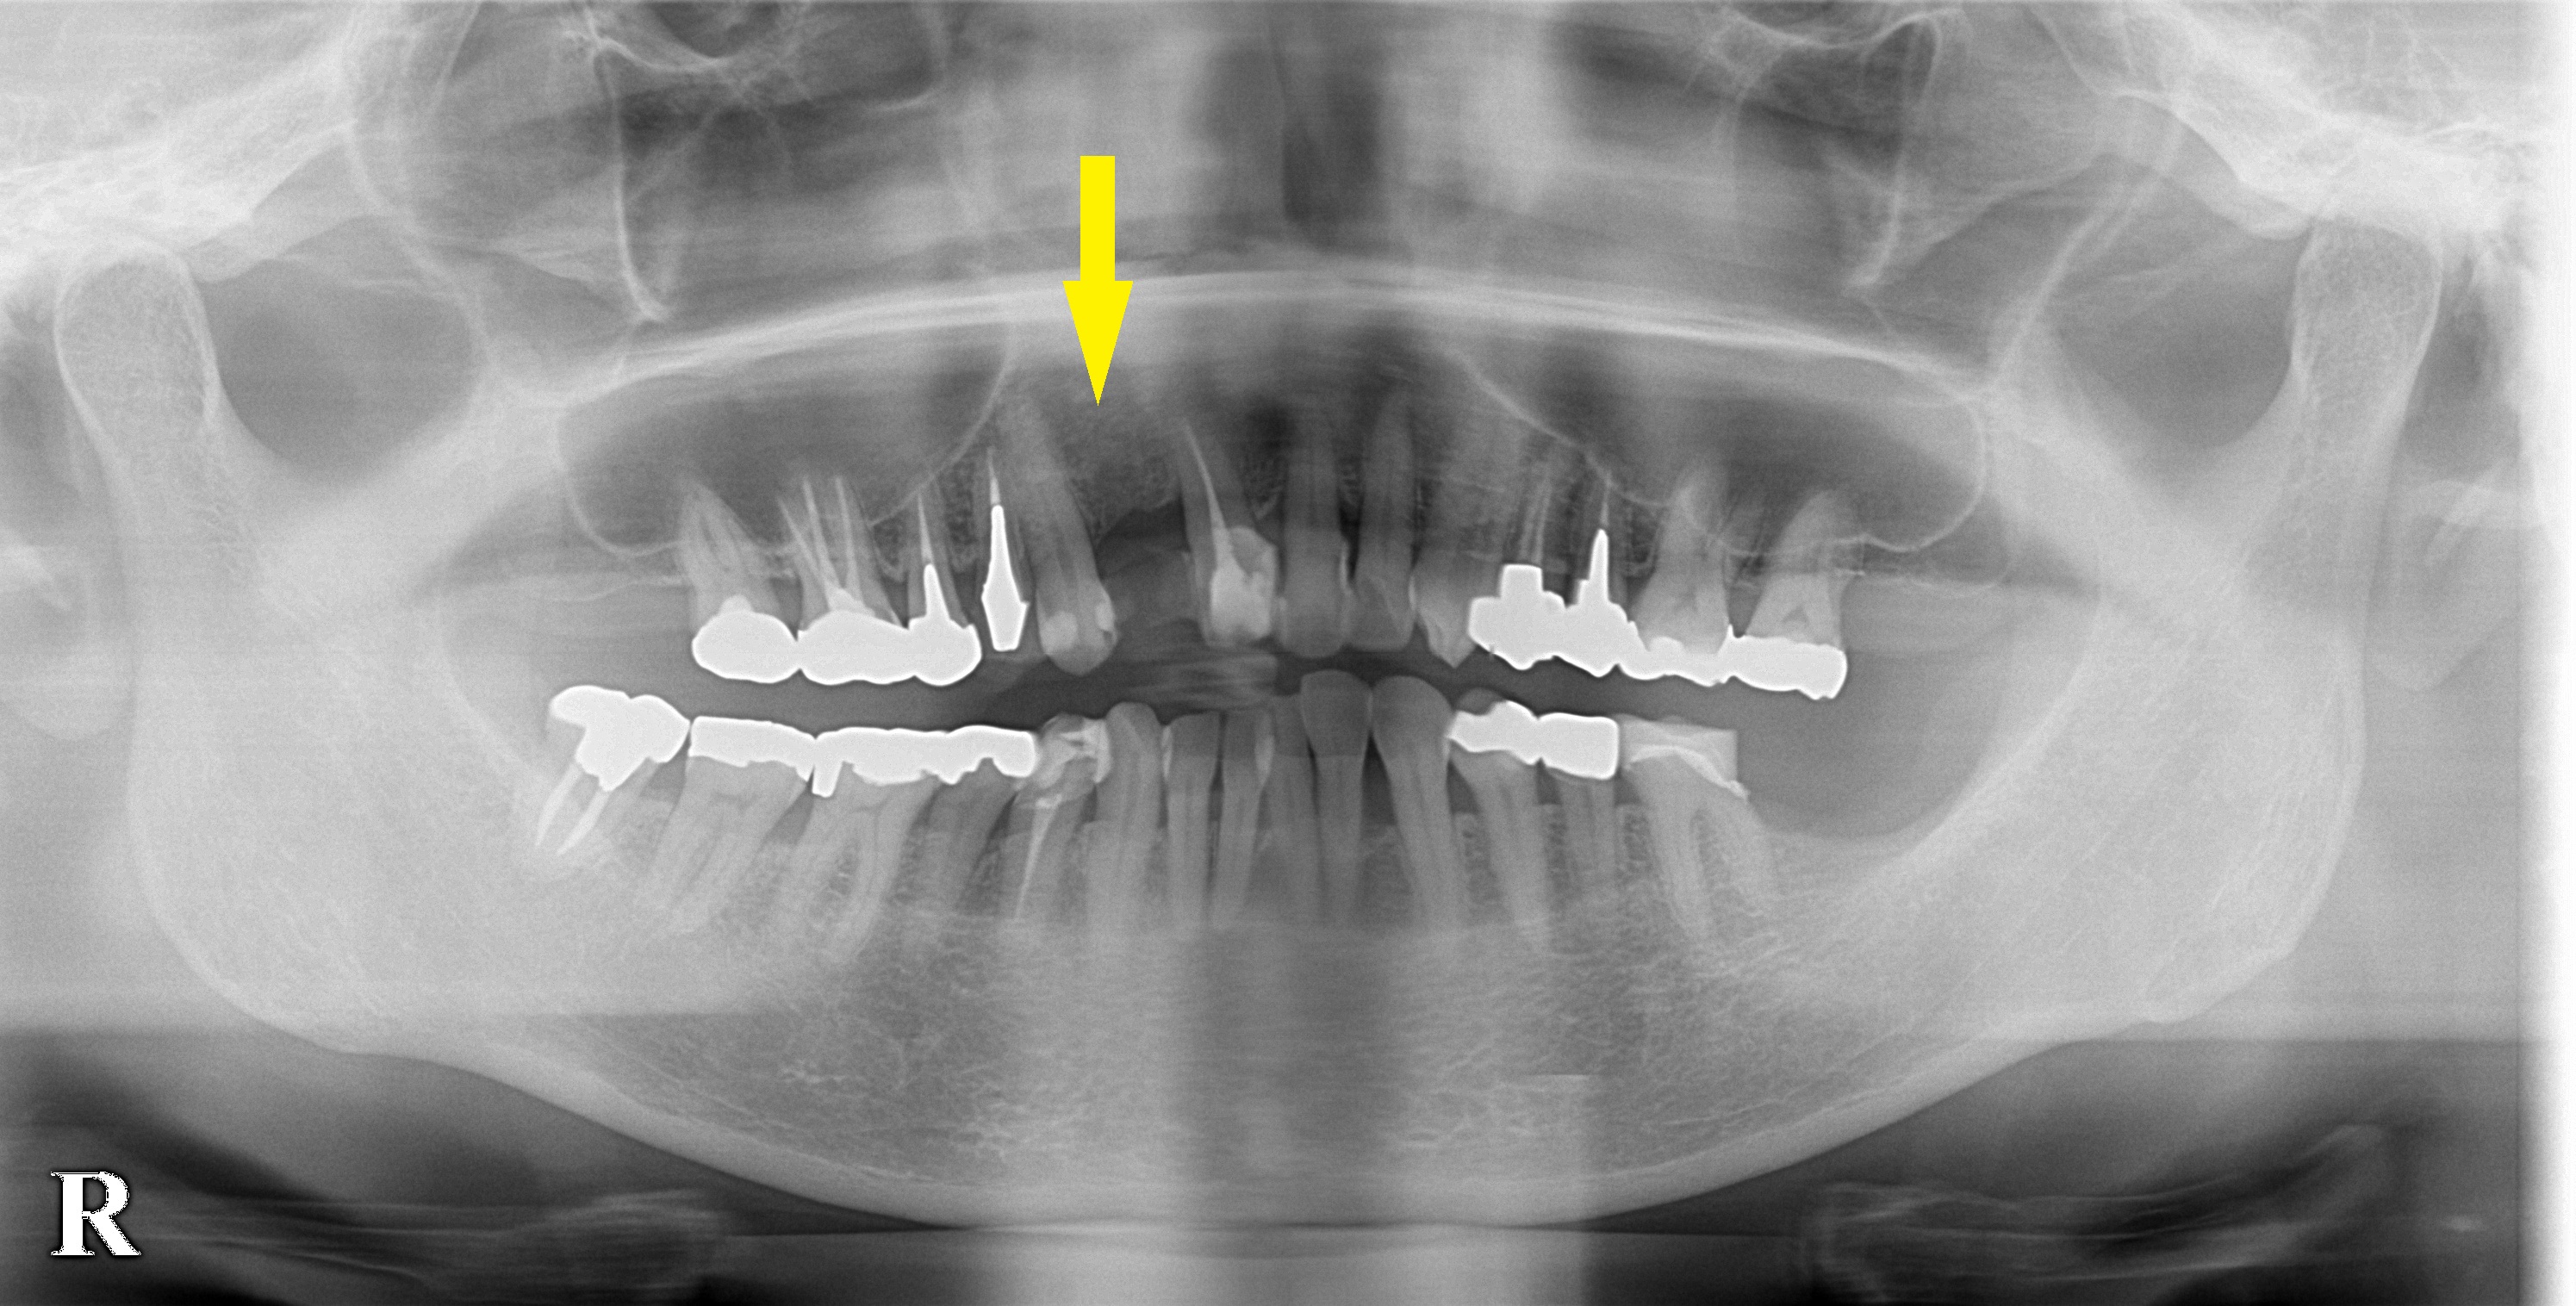

右上顎前歯の虫歯がひどく、歯根に膿がたまって、抜歯に至ったそうです。

インプラント治療を希望されて来院されたのですが、レントゲン、CTを撮ってみると、骨の高さは十分なのですが、厚みが不足していて、通常のインプラント埋入は不可能でした。

そこで、インプラントの外側に人工骨を補填して、骨幅を増生する手術を併用する必要があると説明させていただき、この方法で了承されましたので、本日インプラント埋入術および骨造成術を行いました。